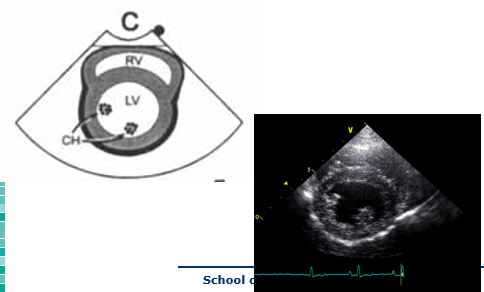

What view?

Right parasternal long axis (RPLA)

4 chamber view

What does this show?

LA size

LV dimensions